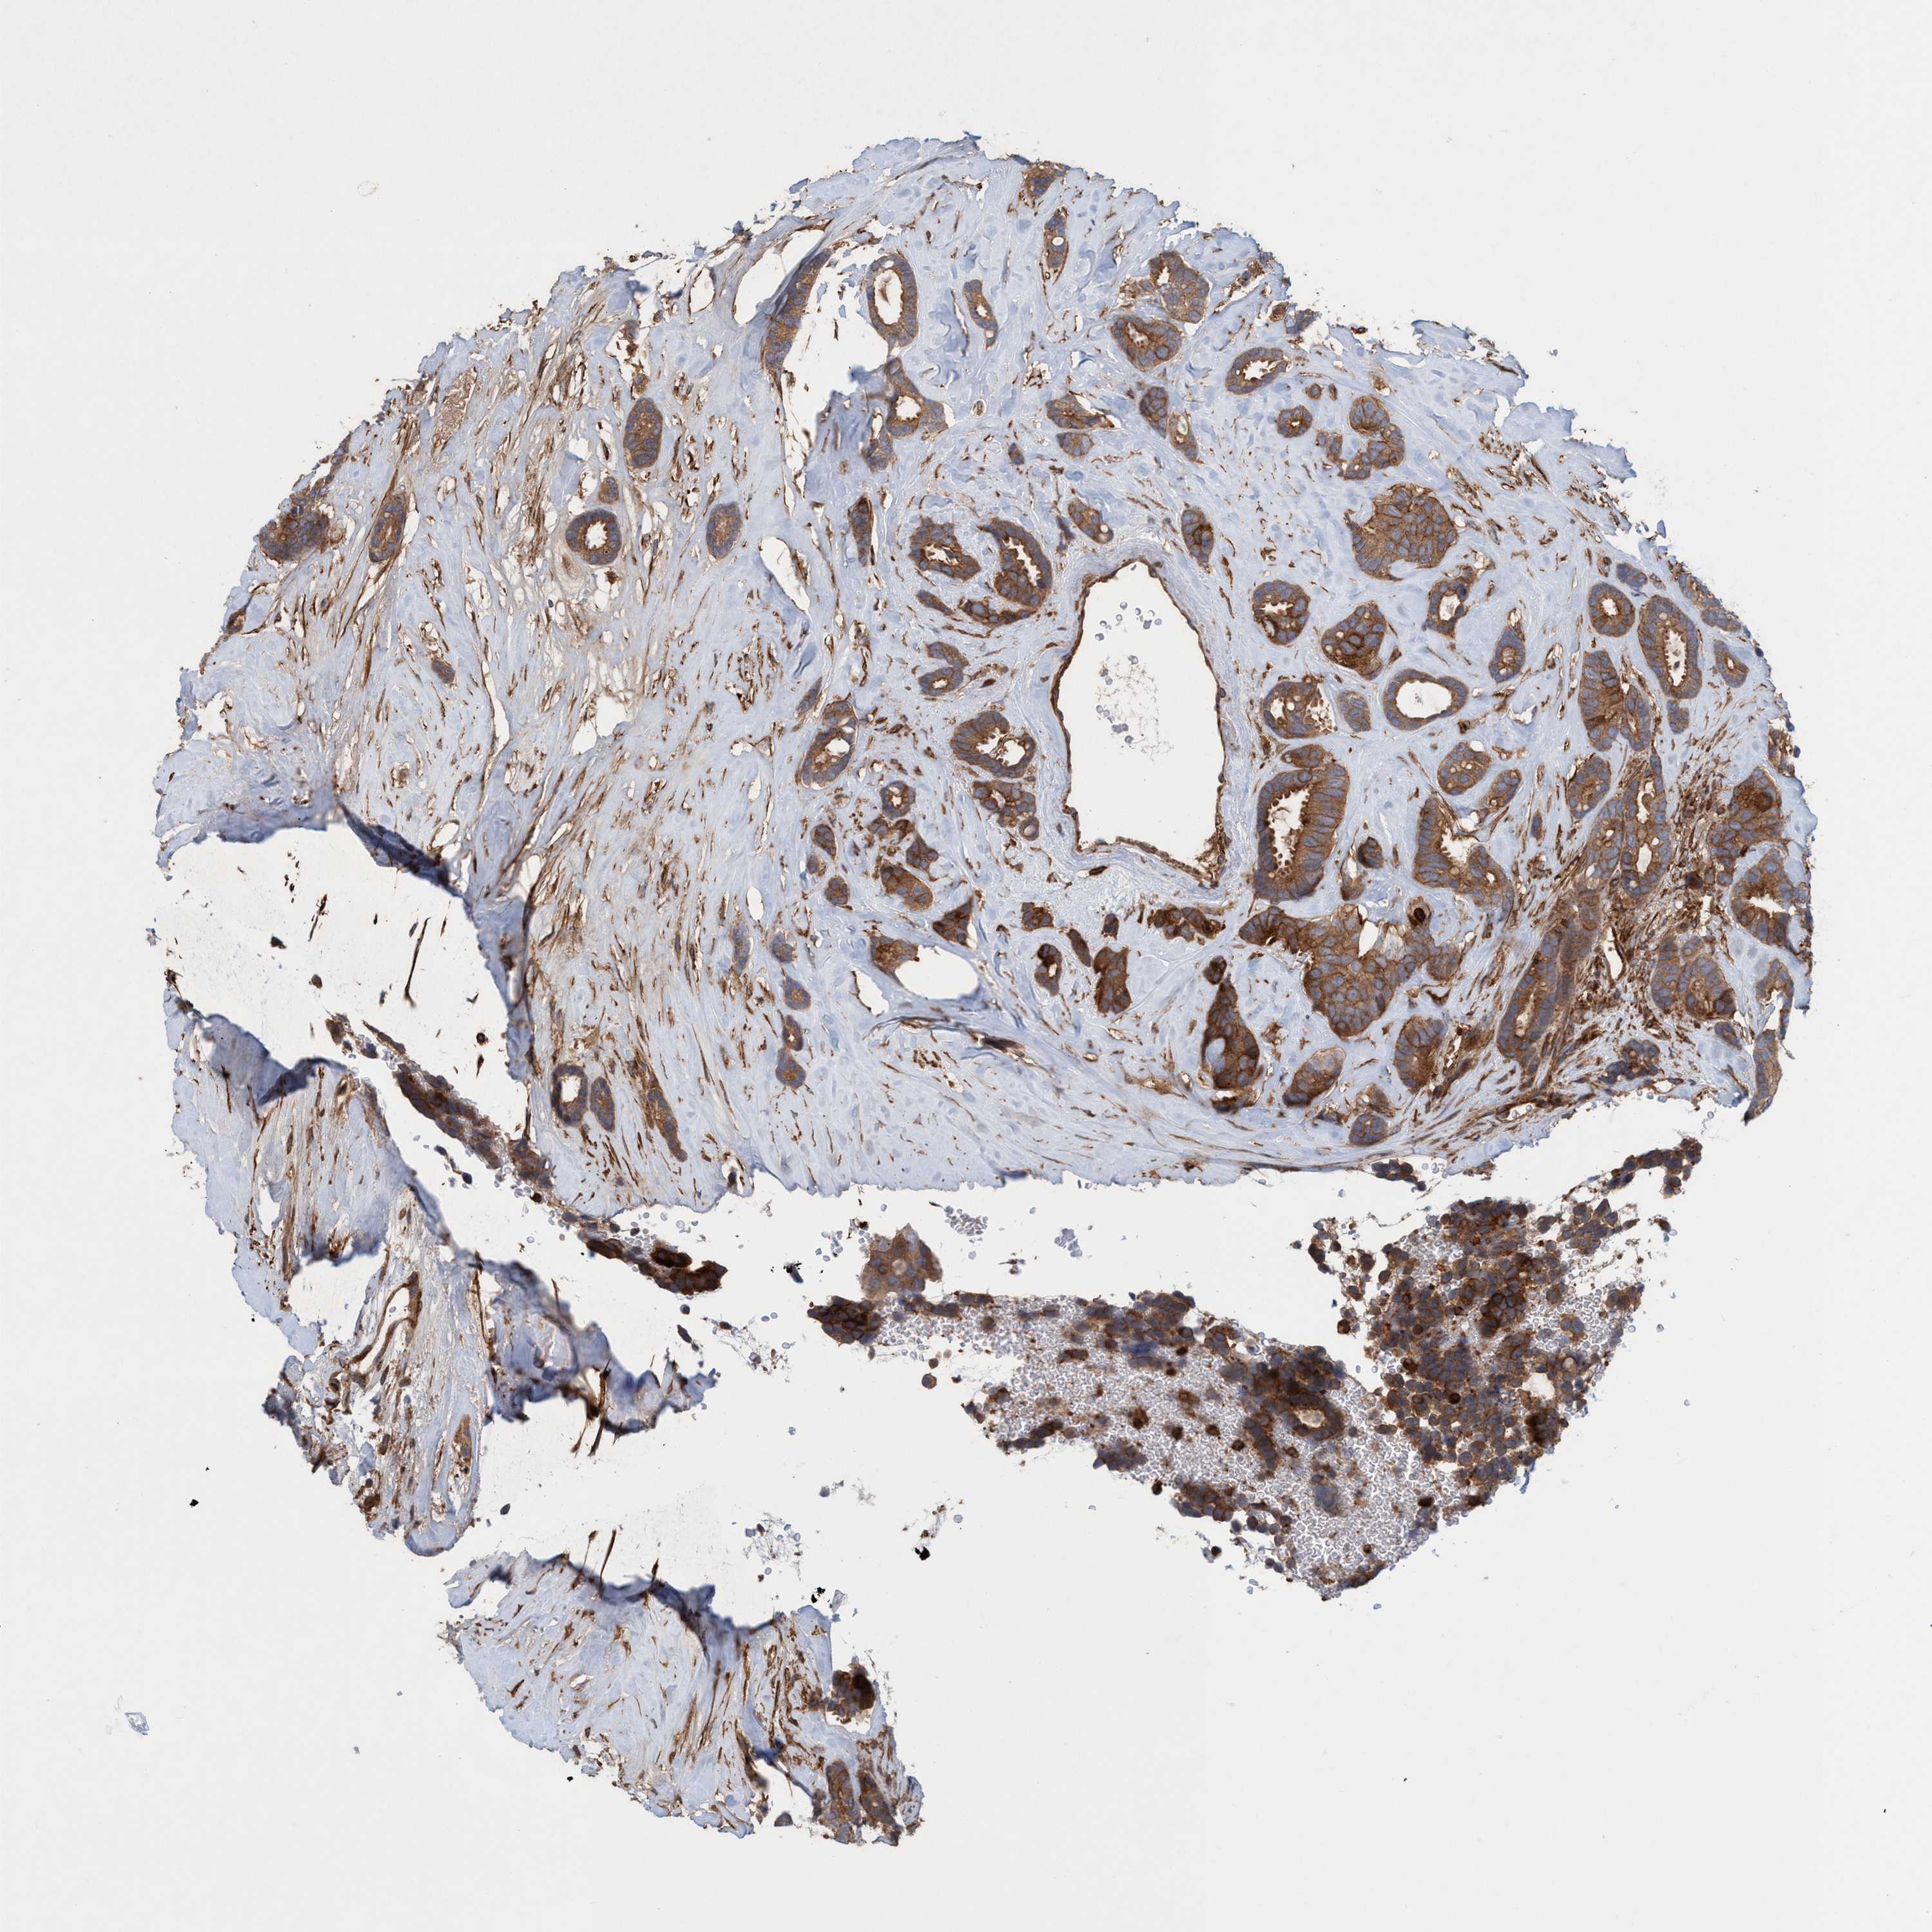

CANCER BREAST CANCER Show tissue menu

BRCA TCGA BRCA VALIDATION PROTEIN EXPRESSION

Breast cancer

Breast invasive carcinoma